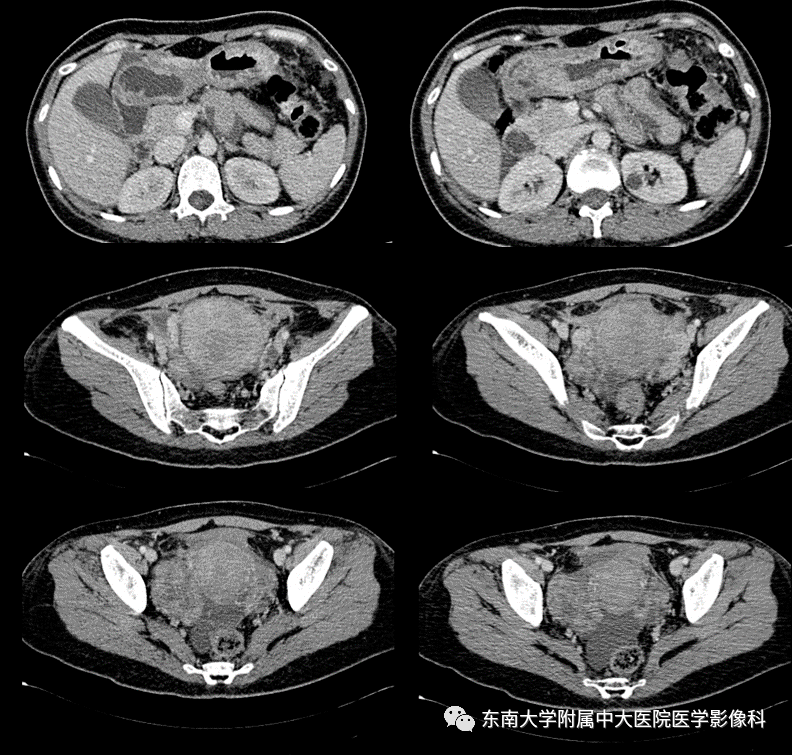

上腹部ct平扫,发现胃窦小弯侧壁增厚. 建议增强ct扫描

ct:肿瘤位于胃窦后壁

断层ct显示胃窦部不规则胃壁增厚(arrow),无胃周脂肪浸润,提示t2期

平扫胃窦部病灶及肿大淋巴结